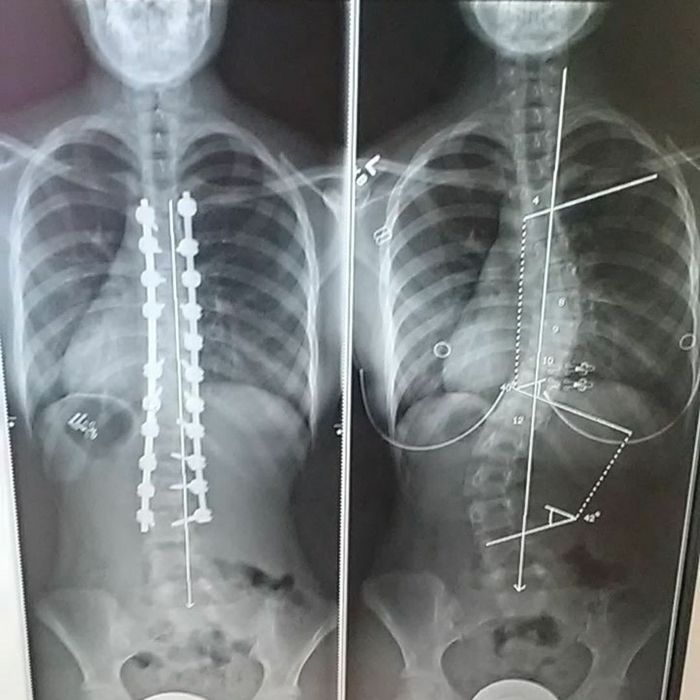

Kondisi ini ditandai dengan melengkung atau membeloknya tulang belakang ke samping. Pengertian skoliosis skoliosis adalah suatu kelainan bentuk pada tulang belakang dimana terjadi pembengkokan tulang belakang ke arah samping kiri atau kanan. Sudut kelengkungan pada skoliosis dapat terjadi dalam rentang kecil hingga besar. Biasanya, tulang punggung penderita skoliosis akan membentuk huruf ‘s’ atau ‘c’. Skoliosis adalah istilah yang kita gunakan untuk mengacu pada kelengkungan lateral (ke samping) tulang belakang yang tidak bisa lagi diperbaiki sepenuhnya.